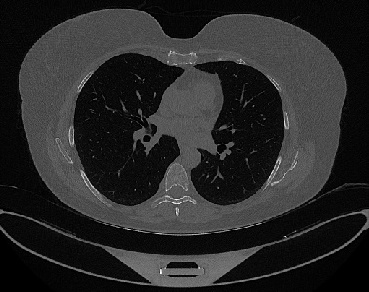

Figure 1 shows four CT scan slices, two from a non-COVID-19 CT scan, on the left and two from a COVID-19 scan, on the right. Bilateral ground glass regions are seen especially in lower lung lobes in the COVID-19 slices.